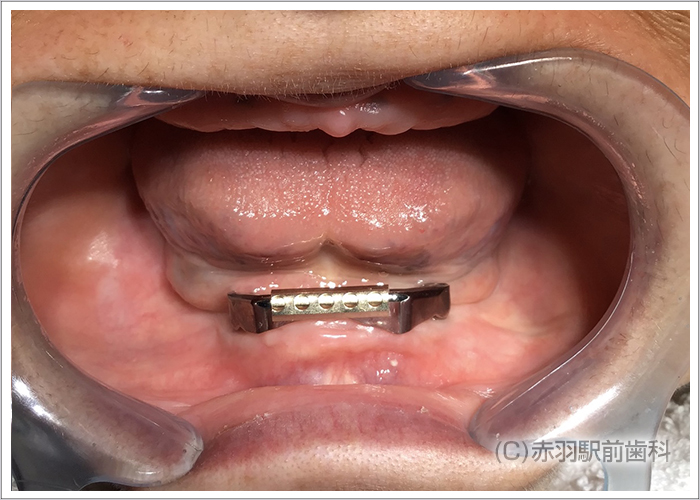

シミュレーション通りの位置にインプラント手術を完了しました。上下ともに両サイドのインプラントはオールオン4特有の傾斜埋入をしています。

インプラント手術完了後にSRAアバットを装着した状態の口腔内です。固定式の仮歯が当日に入ります。

上下に最終的な上部構造の人工歯をスクリュー固定した状態です。内部の見えない部分をチタンフレームで補強して歯肉をハイブリットセラミックで加工。人工歯はジルコニアの歯を1本ずつ仕上げて完成しました。